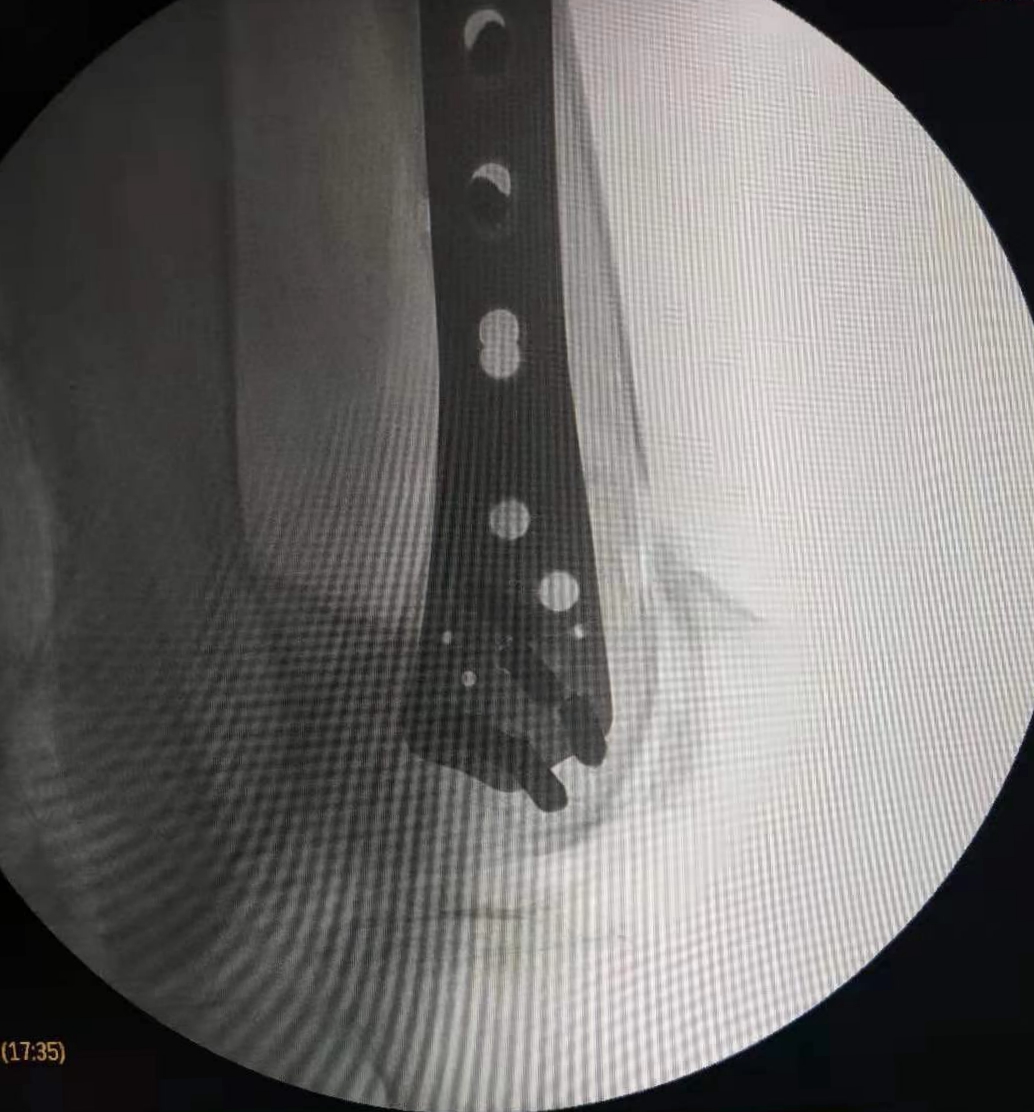

在这个寒冷的初冬,昨日按摩视频 骨二科收治了一名特殊的患者,我院88岁高龄退休老专家,老人在家摔伤导致股骨髁上粉碎性骨折,拒绝去家附近的大医院,专程来我院骨二科就诊。

郭华副院长、张延平主任对病人进行了详细、全面的查体分析,因患者年龄较大,骨折严重再加上老年骨质疏松,骨折部位极易损伤后方血管,考虑患者病情的特殊性,骨二科拟行急诊手术治疗。术前,对患者进行了全面、细致的手术风险及效果评估,按照我科老年患者的优化诊疗标准流程,制定了精准的手术方案,包括风险预案、围手术期准备及护理措施,准备完成后,在急诊进行手术治疗,手术历时2小时。手术顺利、安全完成,目前患者在我科积极术后康复治疗。